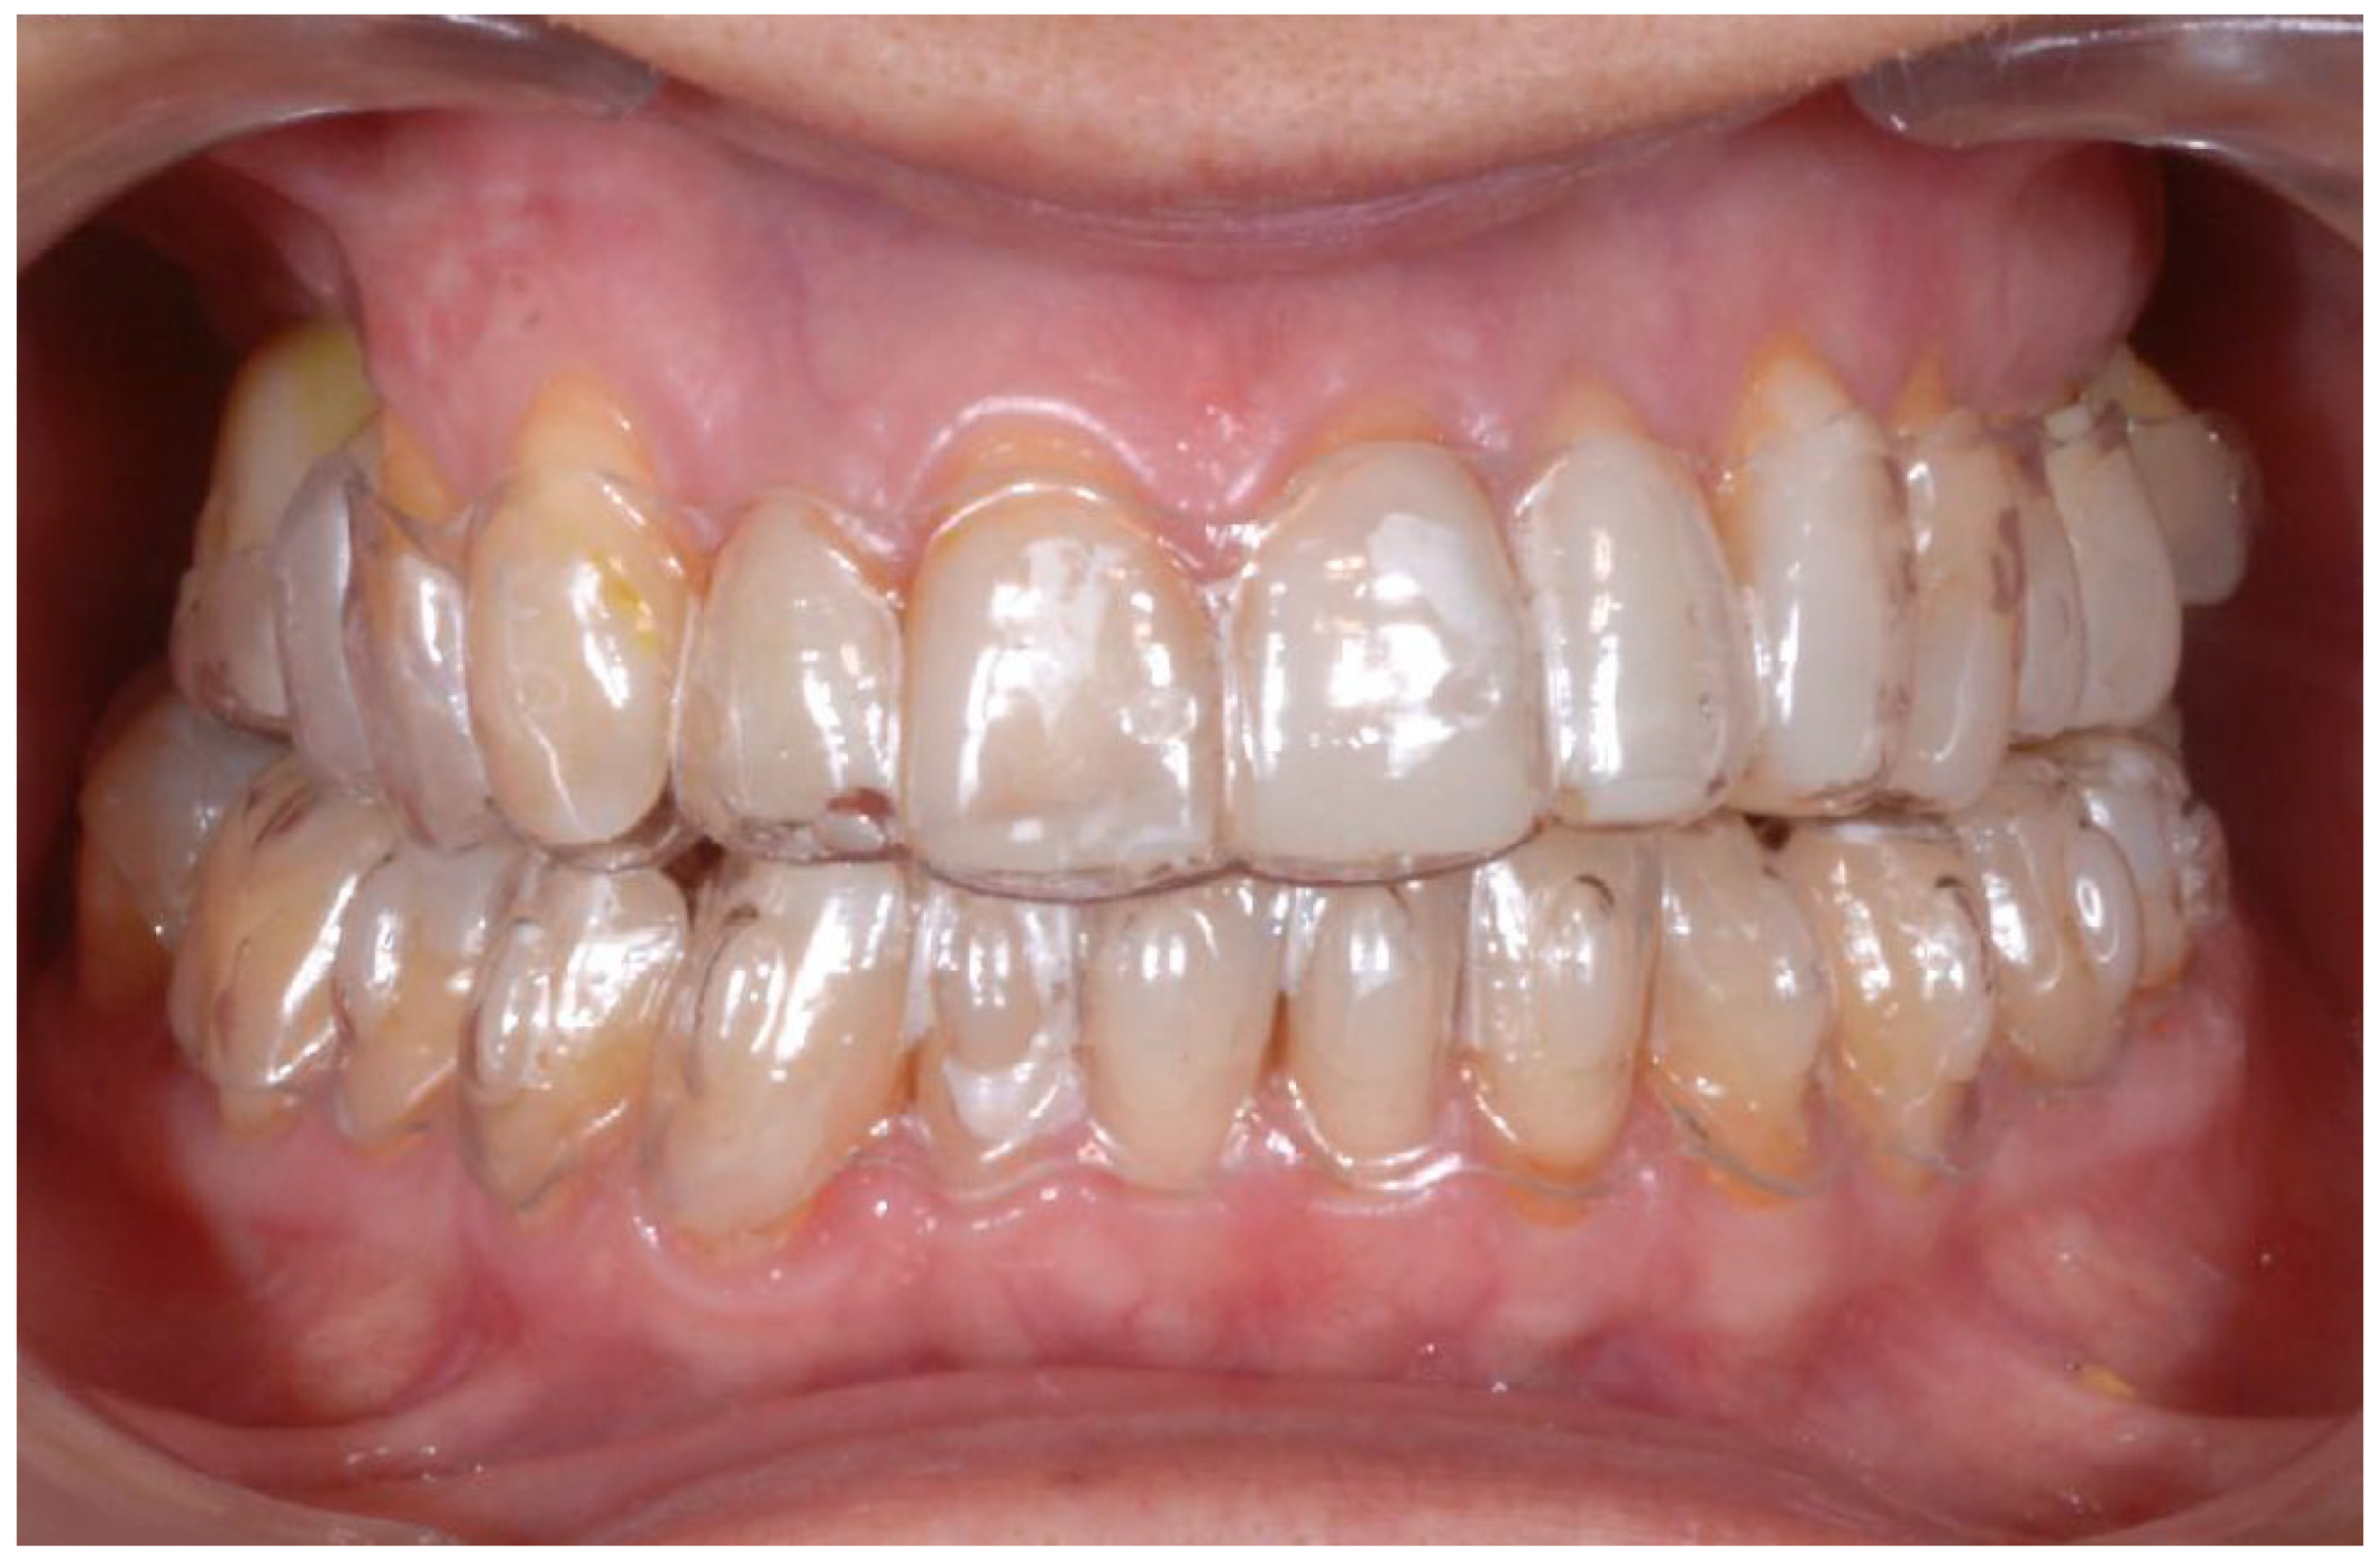

2.2. Clinical Example

2.3. Outcome Achieved